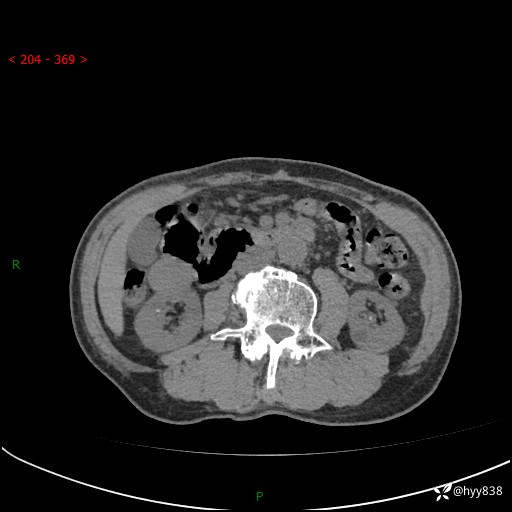

辅助检查:CT

临床诊断:肾肿物

肾脏CT平扫

增强(皮质期+髓质期+排泄期)

三期CT值:132hu 107hu 81hu